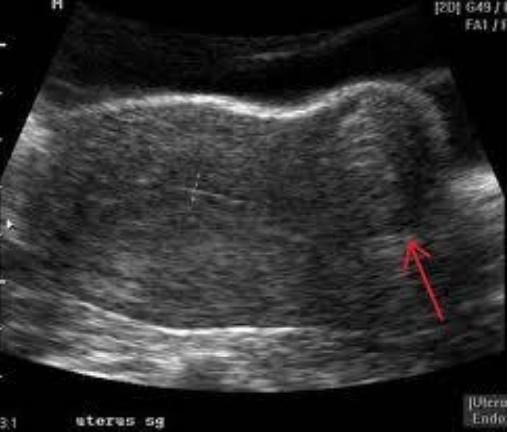

Enfermedades Utero

Leiomyosarcoma Uterino

Por sonografía se ven:

Comprenden 5% de todas las malignidades uterinas

Derivado de músculo liso, se piensa surge de un myoma preexistente

Comunes en el fundus, más frecuentes luego de los 50 años, crecen rápidamente.

Por sonografía se ven complejos mayormente sólidos.

Cuidado con el agrandamiento de myomas especialmente en mujeres posmenopáusicas

Leiomyosarcoma (imagen)